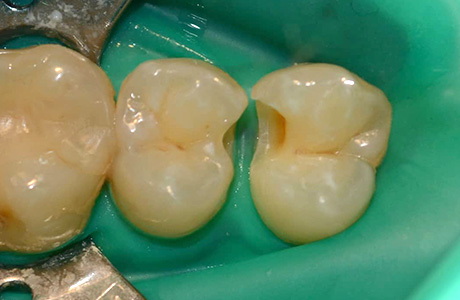

До и после лечения

В нашу клинику обратилась пациентка, которую беспокоили болевые ощущения слева сверху во время приёма сладкой или кислой пищи. В процессе осмотра и диагностики было установлено, что причиной болей и дискомфорта является хронический средний кариес 14, 15 зубов.

Процесс работы

Ход работы:

- применение инфильтрационной анестезии;

- механическая обработка кариозной полости с использованием коффердама;

- пломбирование светокомпозитным материалом;

- микроконтурирование и макроконтурирование пломбы.